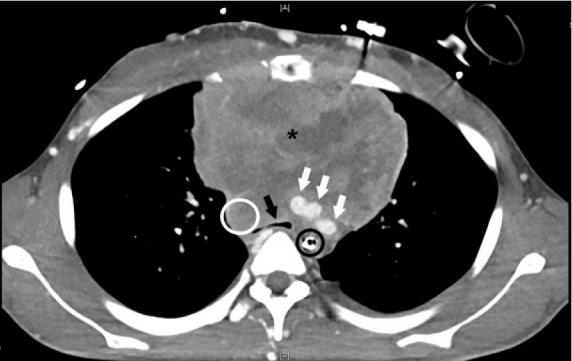

A 20-year-old man with a reported history of asthma presented to the emergency department in cardiac arrest presumed to be caused by respiratory failure.

The patient was discovered to have central airway obstruction and concomitant superior vena cava compression caused by a large mediastinal mass-a condition termed mediastinal mass syndrome. While the patient regained spontaneous circulation after endotracheal intubation, he was challenging to ventilate requiring escalating interventions to maintain adequate ventilation.